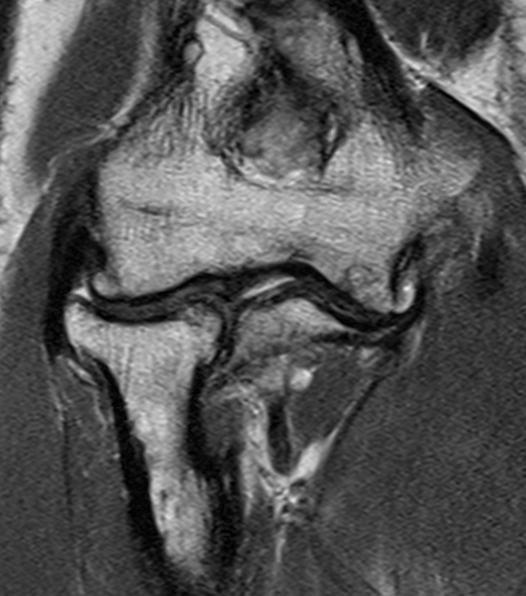

MRI

Useful in detecting early chondral damage

MRI chondral damage radiocapitella joint Chondral thinning anterior ulnohumeral joint

Chondral changes in the radiocapitellar and ulnohumeral joint